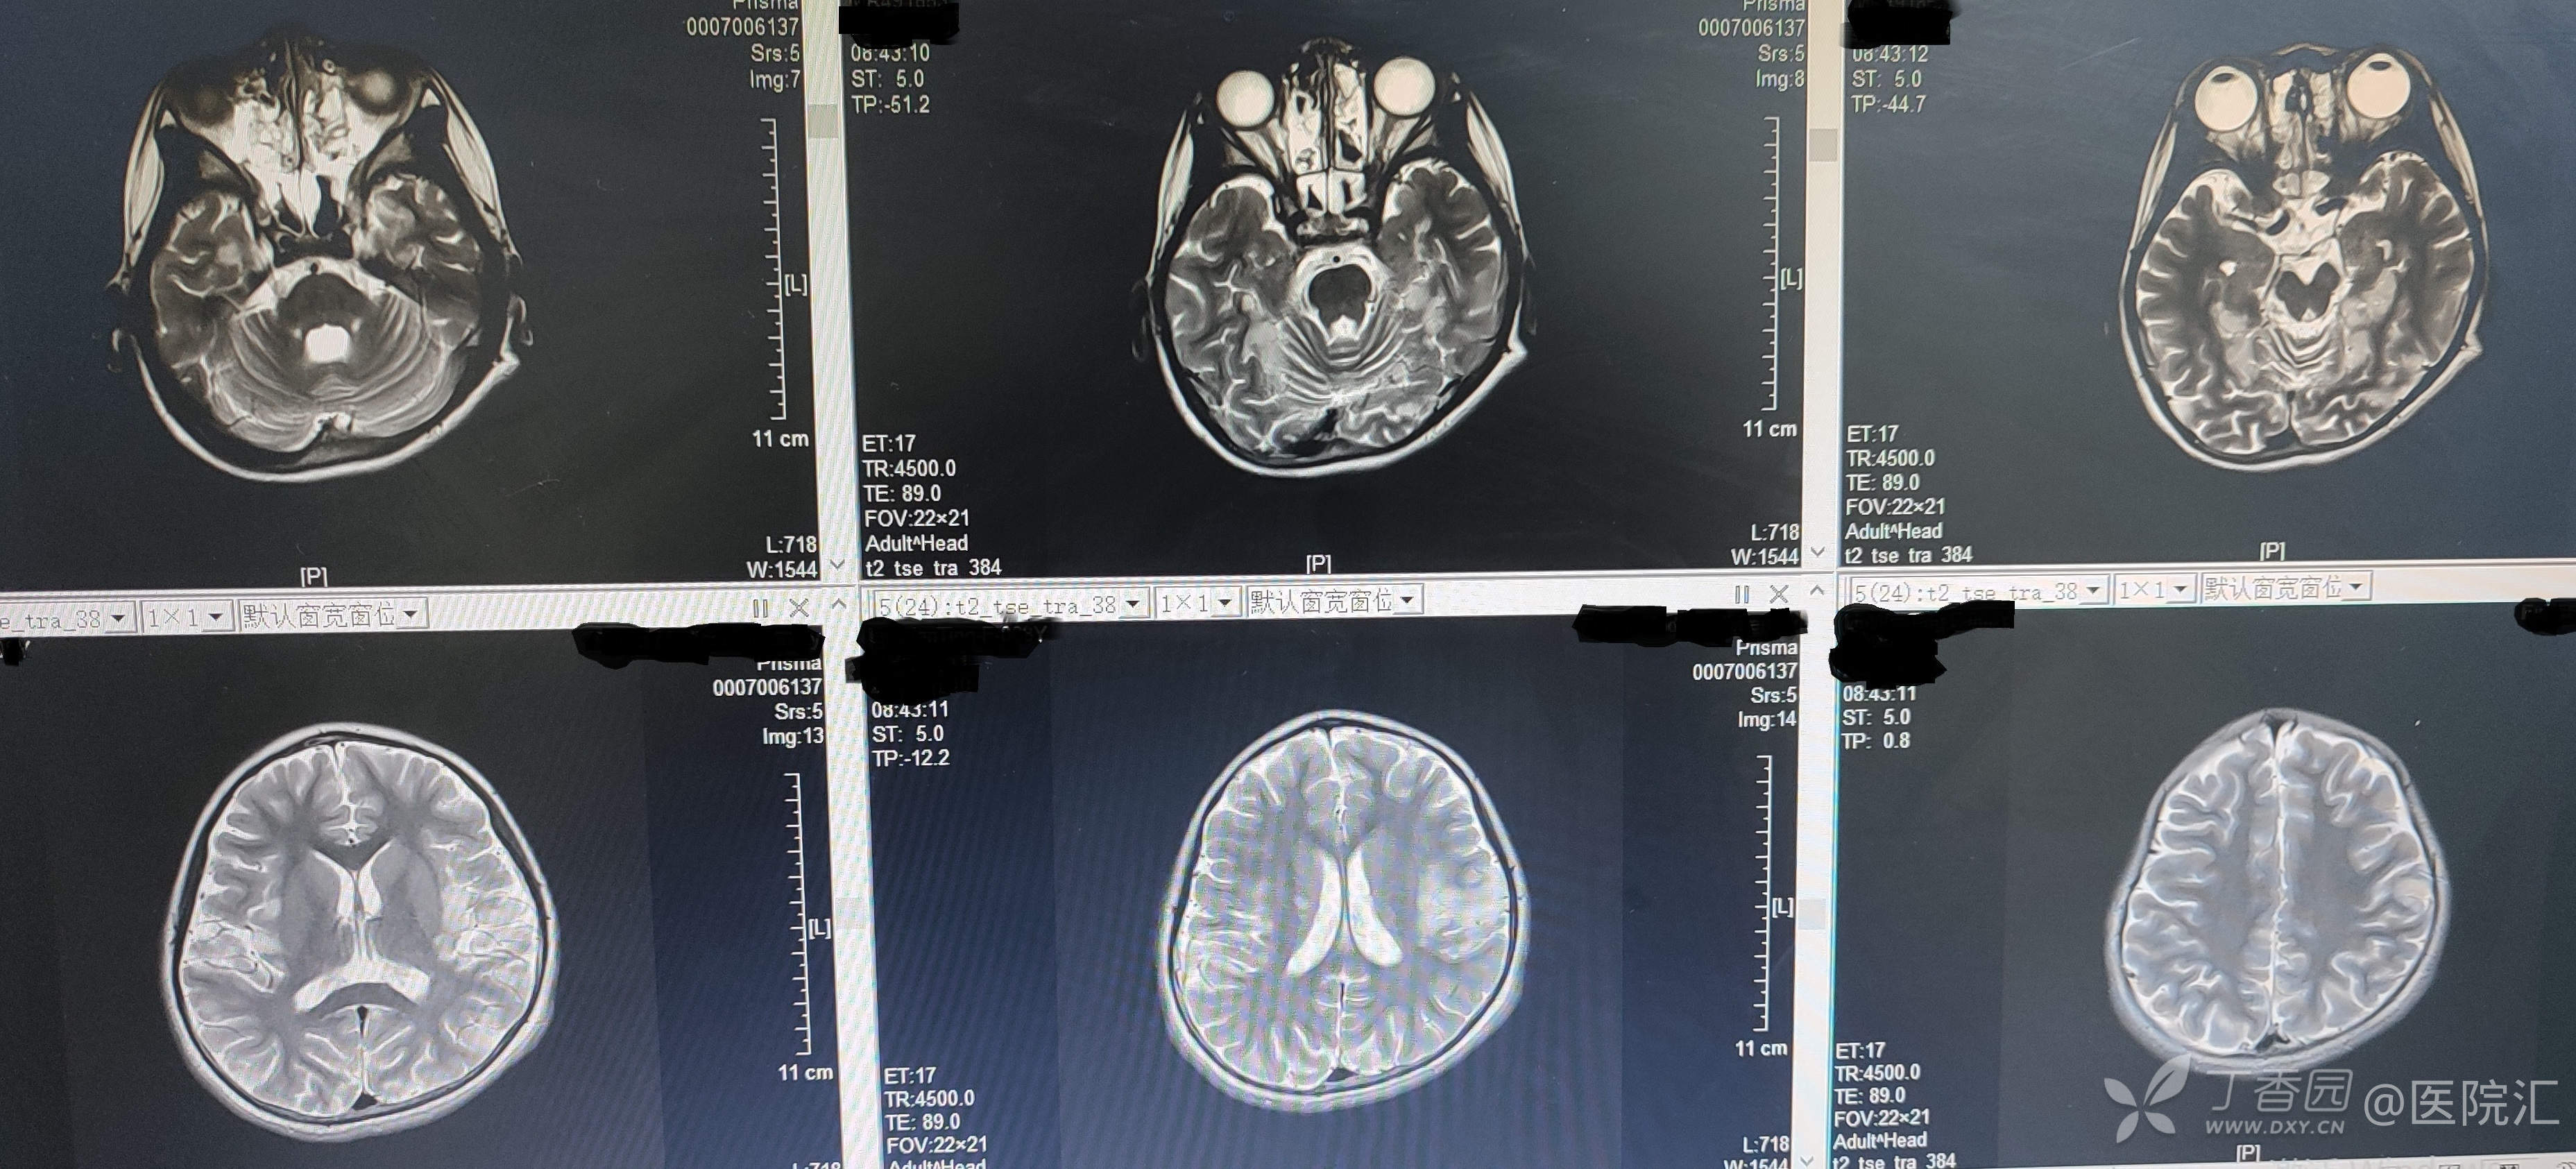

头颅MR:双侧大脑半球异常信号,脑炎?

图2 -3患儿头颅MR表现